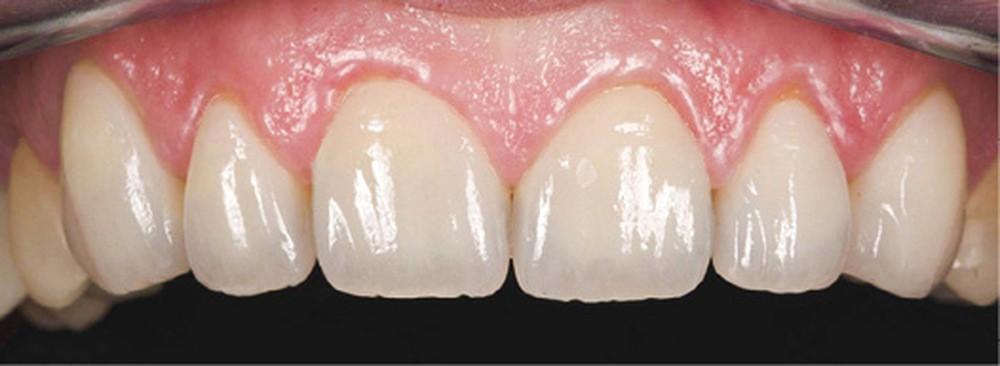

Mme V. est adressée au cabinet dentaire pour une réhabilitation de son sourire. À l’examen clinique, elle présente des usures sur l’ensemble de son maxillaire (fig. 17 et 18). Après évaluation du décalage OIM-ORC, une position de référence en relation centrée avec une dimension verticale augmentée est enregistrée. Pour valider cette position, il est demandé au laboratoire de réaliser un wax-up virtuel. Ce dernier est validé puis transféré en bouche pour essayage (fig. 19 et 20).

Une fois les secteurs postérieurs et l’assise occlusale rétablis, le bloc incisivo-canin antérieur est préparé pour des restaurations adhésives. Là encore, l’assemblage se fait par collage sous champ opératoire. Le suivi est assuré pour contrôler la pérennité du traitement et une éventuelle reprise des usures. Pour ce faire, des rendez-vous cliniques avec réalisation d’une empreinte optique semestrielle sont programmés. La précision de l’empreinte permet ainsi de dépister le moindre phénomène d’usure (fig. 24 à 27).